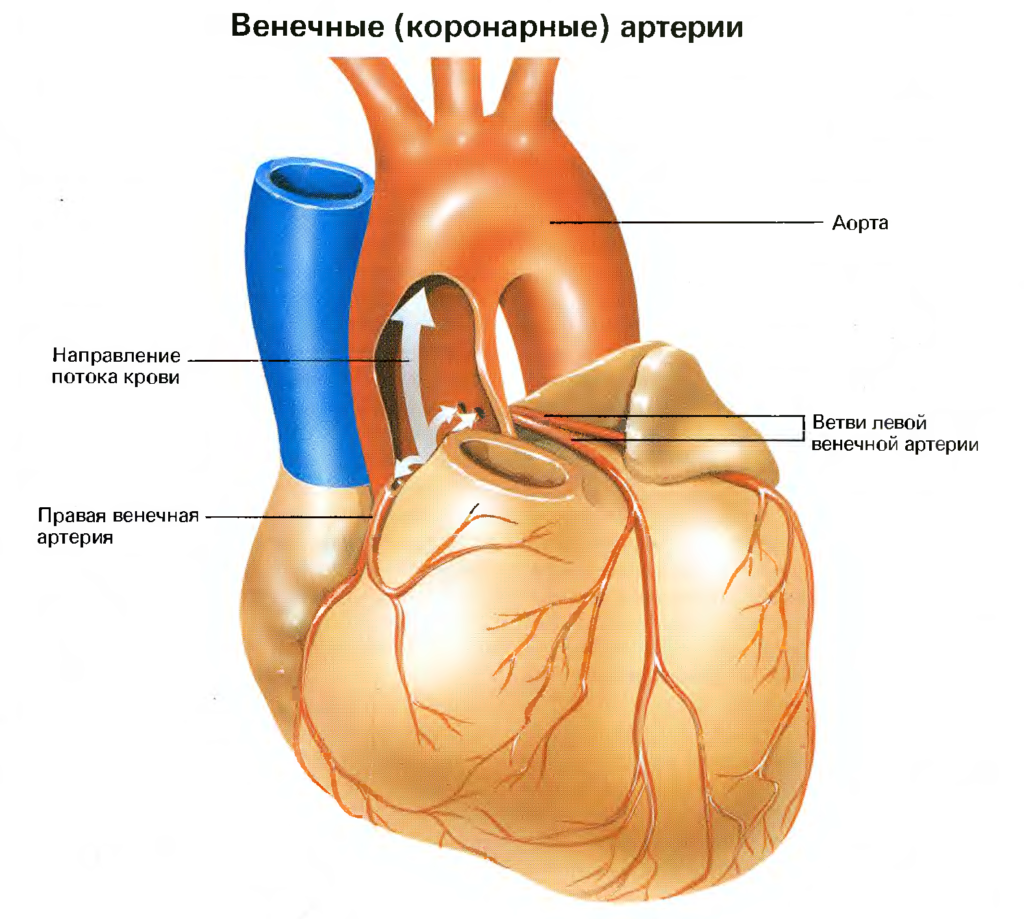

Анатомия коронарных артерий: КТ-изображения